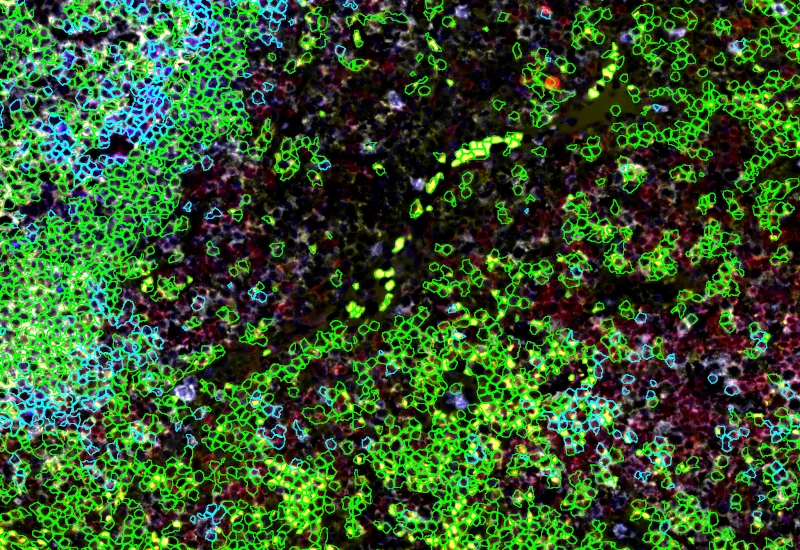

Phenotype 1 and Phenotype 2 detection

Phenotype 1 to 2 proximity 0-5μm

Phenotype 1 to 2 proximity 5-25μm